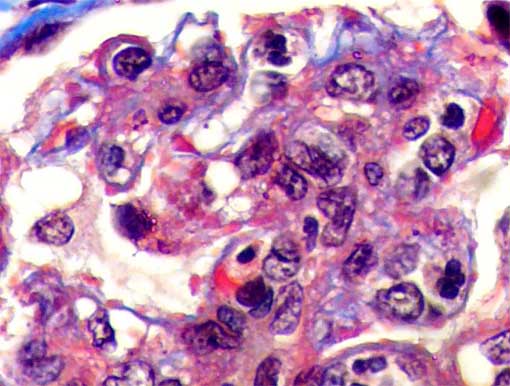

Figure 6.

Masson's trichrome stain, X1,000.